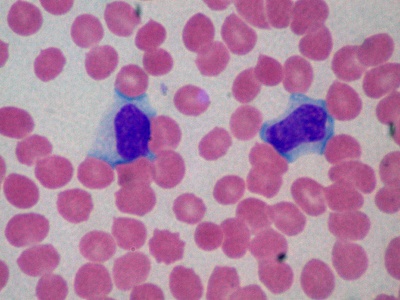

HIV/AIDS

HIV infects immune cells and can progress to AIDS, marked by severe immune failure and opportunistic infections. Global pandemic spread by sex, blood and perinatal routes. Antiretroviral therapy controls virus and prevents progression; no vaccine yet, prevention reduces transmission.